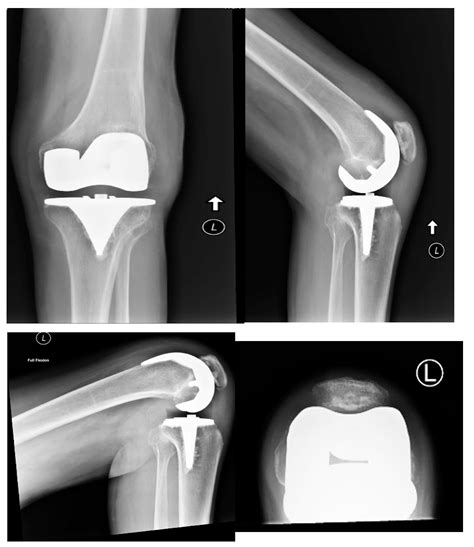

• Implant Placement: Securing the metal and plastic components that act as the new joint.

Many patients worry about pain management, the appearance of the surgical site, and the longevity of the implant. By watching a professional Total Knee Replacement video, you can witness the precision involved in modern robotics-assisted surgery, which often leads to smaller incisions and more accurate alignment. This knowledge helps address common misconceptions, such as the idea that the entire knee is “replaced.” In reality, the procedure is more of a resurfacing of the joint, where only the diseased bone and cartilage are removed and replaced with high-durability prosthetic materials.